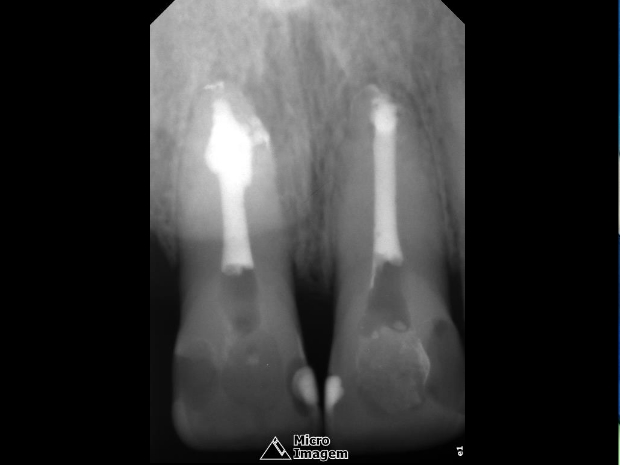

A obturação foi realizada pela técnica termomecânica Híbrida de Tagger (figuras 7 e 8) por meio do emprego de GutaCondensor (Maillefer/Suiça), cones de guta-percha TP (Dentsply/Brasil) e cimento obturador à base de M.T.A. Fillapex (Angelus/Brasil) (figura 9).

Após a termocompactação, realizou-se o corte da obturação, condensação vertical com o uso de calcadores a frio, limpeza da câmara pulpar e restauração provisória imediata do mesmo (figura 10). Observou-se radiograficamente selamento de ramificações e de áreas reabsortivas, bem como a presença de pós-operatório silencioso.

- Figura 7

- Figura 8